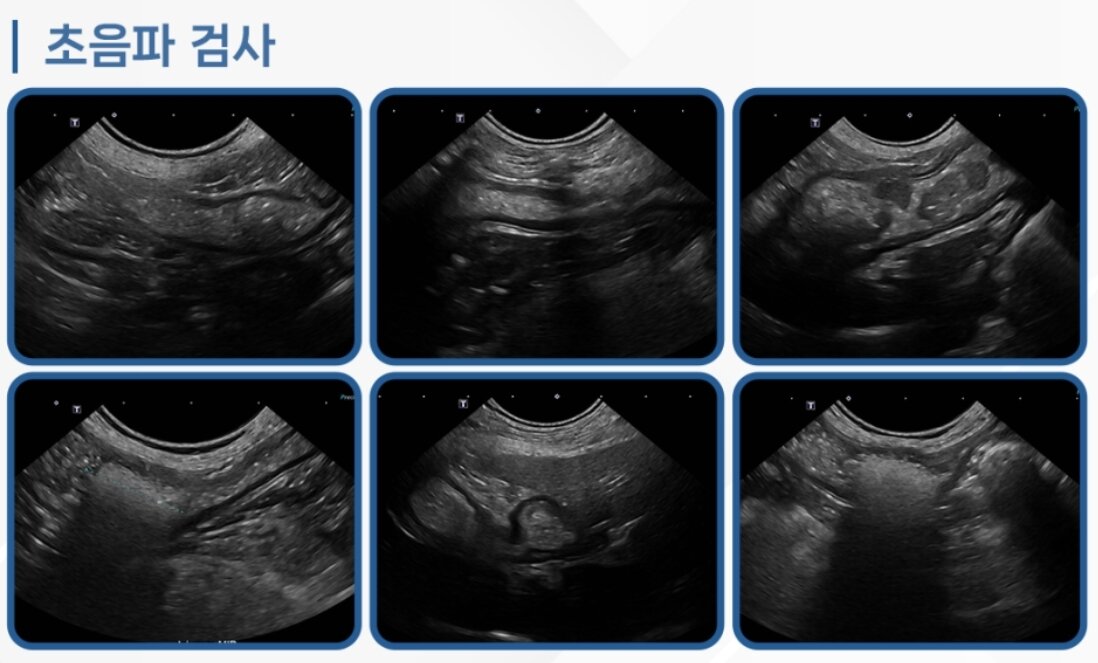

본문 이미지 - 코코는 초음파 검사 결과 장폐색이 진행 중인 상태였다(로얄동물메디컬센터 제공). ⓒ 뉴스1

코코는 초음파 검사 결과 장폐색이 진행 중인 상태였다(로얄동물메디컬센터 제공). ⓒ 뉴스1